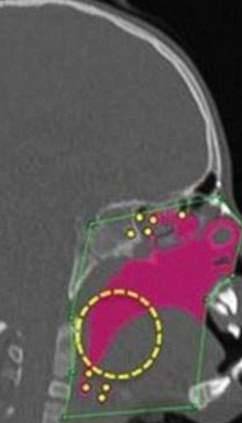

▼他们决定旋转汉娜部分的骨骼,让她的气管能够因此畅通连接,经历一系列的手术并休养后,汉娜终于在近日接受了最重要的气管重建手术,也来到她目标的最后一步。

▼哈波医生成功地执行了这项手术,手术后,汉娜的气管从一开始极为狭窄的状况,终于被扩通!